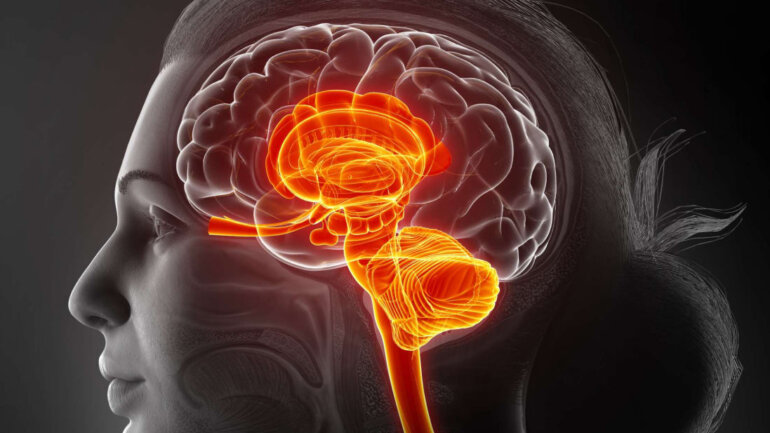

Όταν καταναλώνουμε τροφή, πληροφορίες μεταδίδονται από το γαστρεντερικό σωλήνα στον εγκέφαλο, προκειμένου να προσαρμοστούν τα συναισθήματα της πείνας και του κορεσμού. Με βάση αυτές τις πληροφορίες, ο εγκέφαλος αποφασίζει εάν θα συνεχίσουμε ή θα σταματήσουμε να τρώμε. Το πνευμονογαστρικό νεύρο, που εκτείνεται από τον εγκέφαλο μέχρι τη γαστρεντερική οδό, παίζει ουσιαστικό ρόλο σε αυτήν την επικοινωνία.

Στο κέντρο ελέγχου του πνευμονογαστρικού νεύρου, βρίσκονται διάφορα νευρικά κύτταρα, μερικά από τα οποία νευρώνουν το στομάχι, ενώ άλλα νευρώνουν το έντερο.

«Για να διερευνήσουμε τη λειτουργία των νευρικών κυττάρων, αναπτύξαμε μια γενετική προσέγγιση που μας επιτρέπει να οπτικοποιήσουμε τα διαφορετικά νευρικά κύτταρα και να χειριστούμε τη δραστηριότητά τους σε ποντίκια. Αυτό μας επέτρεψε να αναλύσουμε ποια νευρικά κύτταρα νευρώνουν ποιο όργανο, κάτι που δείχνει ποια σήματα ανιχνεύουν στο έντερο», είπε ο επικεφαλής της μελέτης Henning Fenselau Max Planck Institute. «Μας επέτρεψε επίσης να ενεργοποιήσουμε και να απενεργοποιήσουμε τους διαφορετικούς τύπους νευρικών κυττάρων για να αναλύσουμε την ακριβή λειτουργία τους».

«Ένας από αυτούς τους τύπους κυττάρων ανιχνεύει το τέντωμα του στομάχου και η ενεργοποίηση αυτών των νευρικών κυττάρων κάνει τα ποντίκια να τρώνε σημαντικά λιγότερο», είπε ο Fenselau. «Αναγνωρίσαμε ότι η δραστηριότητα αυτών των νευρικών κυττάρων είναι το κλειδί για τη μετάδοση σημάτων αναστολής της όρεξης στον εγκέφαλο και επίσης στη μείωση των επιπέδων σακχάρου στο αίμα».

Μια δεύτερη ομάδα νευρικών κυττάρων νευρώνει κυρίως το έντερο. «Αυτή η ομάδα νευρικών κυττάρων ανιχνεύει χημικά σήματα από τα τρόφιμα που τρώμε. Ωστόσο, η δραστηριότητά τους δεν είναι απαραίτητη για τη ρύθμιση της διατροφής. Αντί αυτού, η ενεργοποίηση αυτών των κυττάρων αυξάνει τα επίπεδα σακχάρου στο αίμα μας», είπε ο Fenselau.

Μια τροφή με πολύ όγκο τεντώνει το στομάχι μας και ενεργοποιεί τους τύπους νευρικών κυττάρων που νευρώνουν αυτό το όργανο. «Σε ένα ορισμένο σημείο, η ενεργοποίησή τους προάγει τον κορεσμό και επομένως σταματά την περαιτέρω πρόσληψη τροφής και ταυτόχρονα συντονίζει τις προσαρμογές των επιπέδων σακχάρου στο αίμα. Η τροφή με υψηλή θρεπτική πυκνότητα τείνει να ενεργοποιεί τα νευρικά κύτταρα στο έντερο. Η ενεργοποίησή τους αυξάνει τα επίπεδα γλυκόζης στο αίμα συντονίζοντας την απελευθέρωση της γλυκόζης του σώματος, αλλά δεν σταματά την περαιτέρω πρόσληψη τροφής».